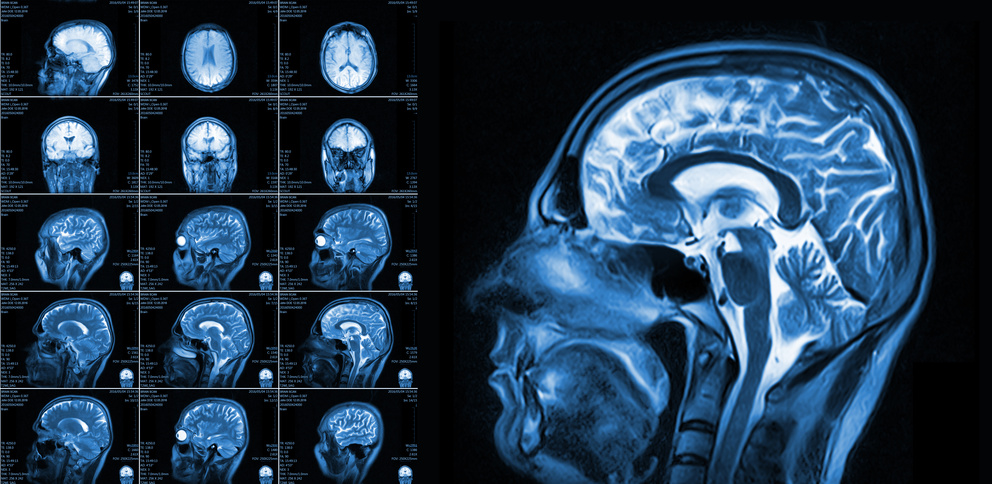

Anatomical Changes in the Brain